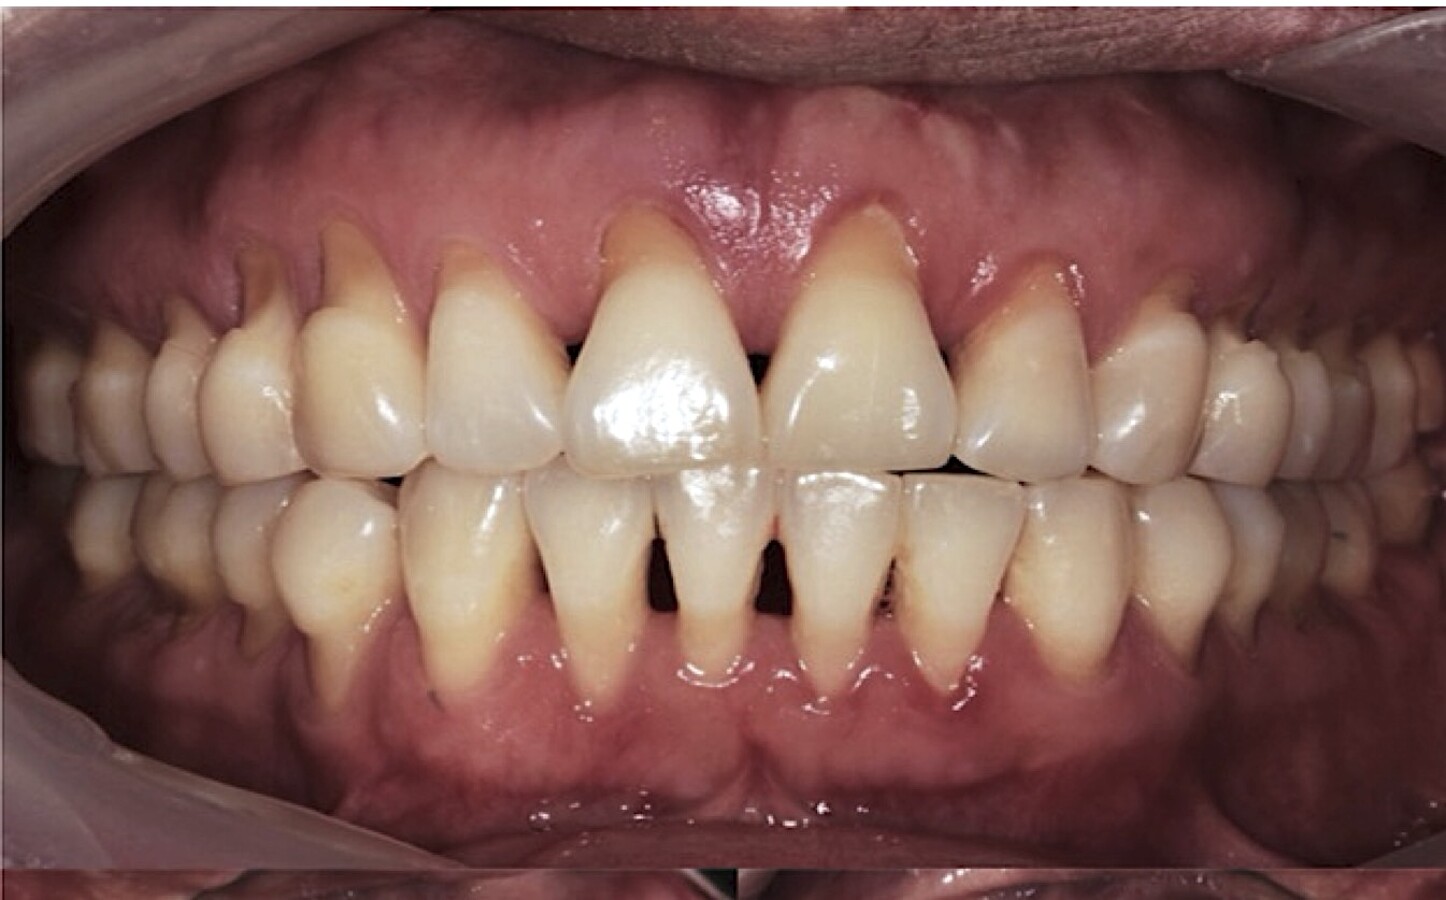

Las lesiones suelen presentarse como defectos cervicales en forma de cuña o cavidades irregulares. En muchos casos son asintomáticas, aunque pueden cursar con hipersensibilidad dentinaria.

Con el tiempo, pueden asociarse a recesión gingival, alteraciones estéticas y compromiso funcional.

Figura 5. A) Paciente de 30 años con LCNC masivas (SPNC). B) Paciente de 32 años con serie de dramáticas recesiones vestibulares. Ambos reportan bruxópatia y dieta acida.